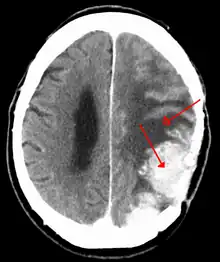

Meningiomas are visualized readily with contrast CT, MRI with gadolinium,[17] and arteriography, all attributed to the fact that meningiomas are extra-axial and vascularized. CSF protein levels are usually found to be elevated when lumbar puncture is used to obtain spinal fluid.